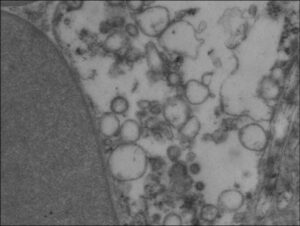

Les vésicules extracellulaires sont des vésicules à membrane libérées par les cellules dans l’espace extracellulaire. Elles comprennent des corps apoptotiques, des microvésicules et des exosomes, désignés maintenant sous les noms de grandes et petites vésicules. Les vésicules extracellulaires sont capables de transmettre des informations d’une cellule à une autre. Nous sommes actuellement en train de déterminer le rôle des vésicules extracellulaires dans la progression et les complications des maladies du foie. Pour ce faire, nous analysons leur rôle dans la communication intercellulaire entre le foie et d’autres organes, ainsi qu’au sein même du foie.

Electronic microscopy view from extracellular vesicles in liver vessels

Les vésicules extracellulaires peuvent également être utilisées comme biomarqueurs. Nous avons démontré que les microvésicules hépatocytaires peuvent prédire l’évolution des patients atteints de cirrhose. (Bissonnette J. Hepatology. 2017 & Payancé A. Hepatology 2018 & Thietart S. Journal of hepatology. 2020).